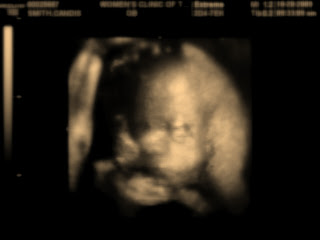

Here is our little boy at 27 weeks. I was amazed at how clear these pictures were compared to the 3D ultrasound I had 2 months ago. His umbilical cord kept sliding across his face. That is why we have the distortion.

wow. cool pictures. we don't get those here. but we get ours tomorrow to find out! stay tuned!!

yay! Can't wait to hear what you are having!